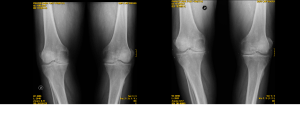

Los implantes de oro periarticulares actúan en las partes blandas de la articulación y es claro el beneficio clínico que se obtiene. Pero hasta ahora no se había objetivado el rol de los implantes a nivel del cartílago hialino en pacientes humanos. A continuación se observan las RX de un paciente octogenario con gonartrosis bilateral y genu varo tras dieciocho (18) meses de colocación de implantes. La buena evolución clínica es paralela a los cambios radiológicos que se observan especialmente en la articulación tibiofemoral interna en donde la degradación cartilaginosa es mayor. Se comparan las radiografías anteriores y posteriores a los implantes, con un aumento significativo de la interlínea articular.